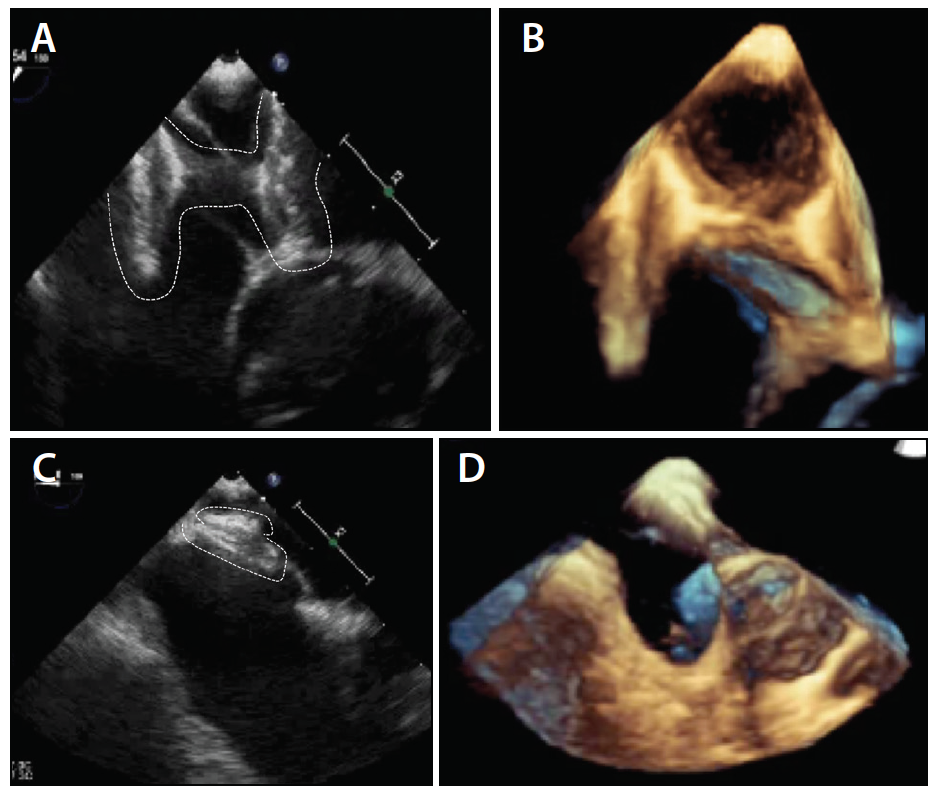

In this patient’s PFO tunnel, the Figulla PFO occluder (Occlutech International AB) did not sit well due to the elongated PFO tunnel that extended to the roof of the atrium and appeared to be splinted open—the tunnel could not be compressed by the device and held the two discs separated (Figure 2). As a result, we decided to perform a transseptal puncture (TSP) in the fossa ovalis and bring the two sides of the PFO tunnel together. The TSP caused a pericardial effusion due to an inadvertent high puncture. After pericardial drainage, an 18-mm Figulla PFO device was placed via the high puncture. The pericardial drain was removed at 24 hours.

Figure 2. Two-dimensional TEE image of the initial device not well aligned to the septum (A). Three-dimensional TEE of the initial device (B). Two-dimensional TEE of the second device well situated on the septum (C). Three-dimensional TEE of the second device (D).